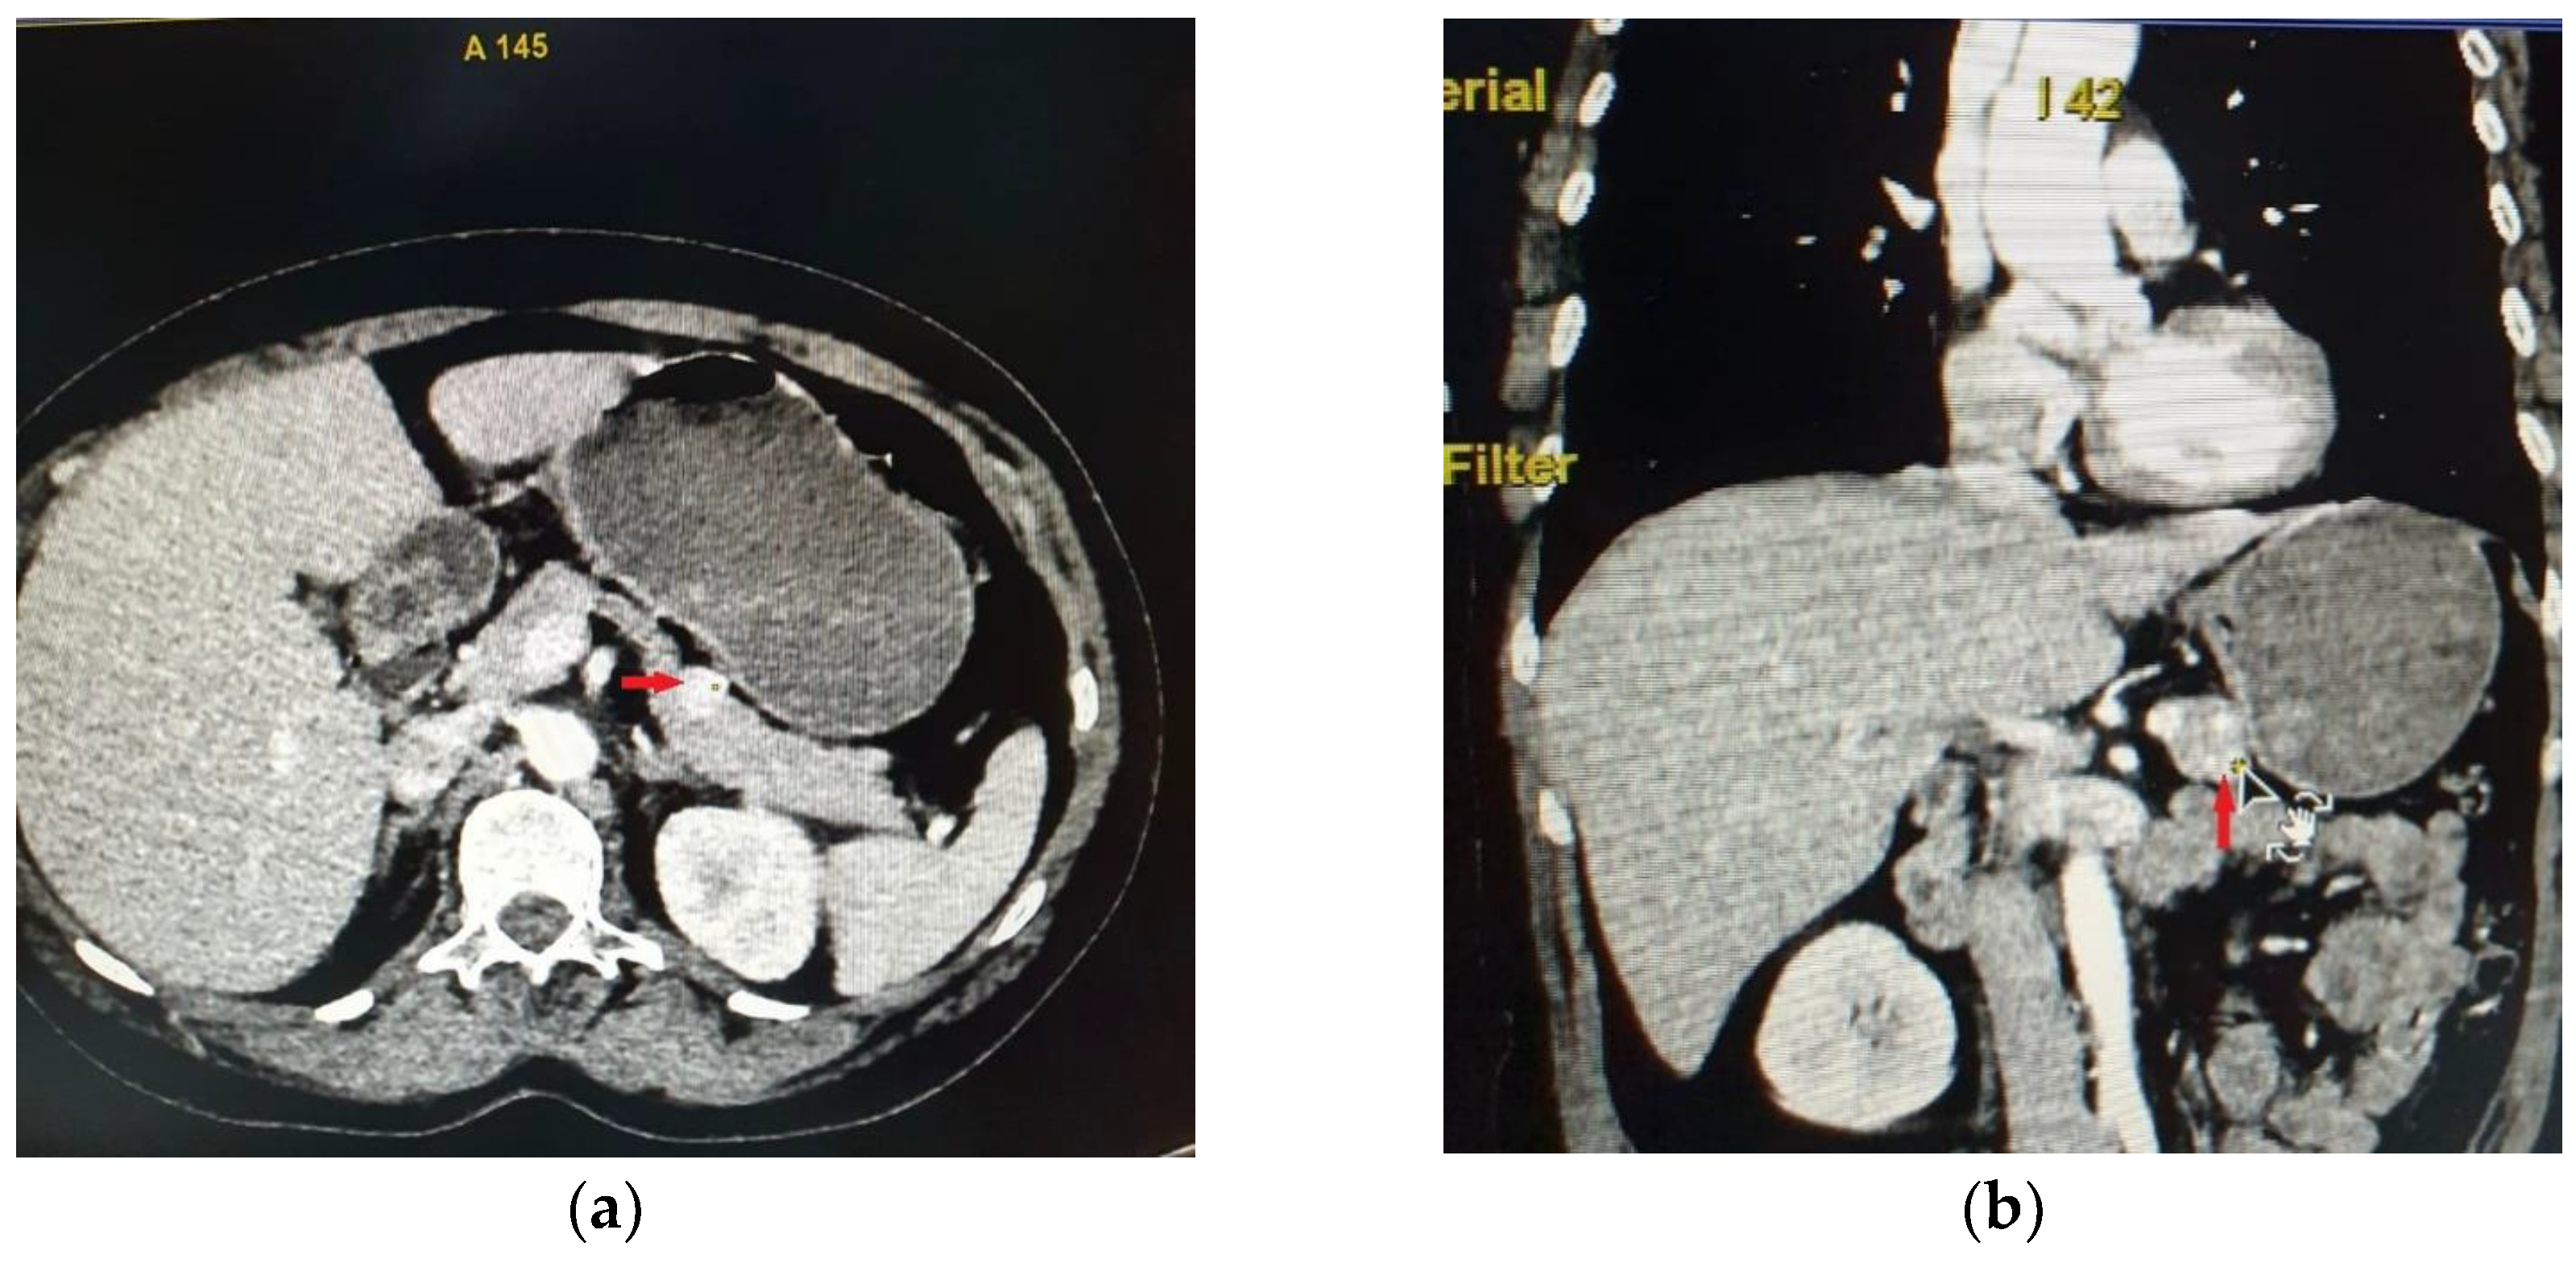

- Popa, S.G.; Ungureanu, B.S.; Gheonea, I.A.; Mitrea, A.; Ardeleanu, C.M.; Ghiluşi, M.C.; Şurlin, V.; Georgescu, E.F.; Georgescu, I.; MoŢa, M.; et al. Pitfalls in diagnosing a pancreatic neuroendocrine tumor: A case report. Rom. J. Morphol. Embryol. 2015, 56, 1495–1502. [Google Scholar]